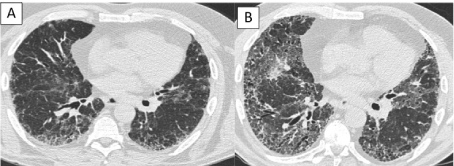

Figure 4: A) HRCT images of patient in Figure 1 are showing the progression of IPF from diagnosis and B) 2 years later. View Figure 4

Figure 6: A) HRCT images of patient in Figure 2 are showing the progression of IPF from diagnosis and B) 3 years later. View Figure 6

Totally 51 patients were included in this study; 35 (68.6%) were male and 16 (31.4%) were female. The mean age was 70.8 years (min, 50-max, 86). The mean FVC, FEV1 and FEV1/FVC were 1970 ml (53%), 1860 ml (63%) and 94.4%, respectively. The diagnostic efficacy of chest roentgenograph was 58.7% in patients with IPF. The radiologic progression during several years in patients with IPF were shown in Figure 3, Figure 4, Figure 5 and Figure 6. The most common comorbidity was malignancy (10.8%) in patients with IPF and lung cancer with IPF was shown in Figure 7. The number of cases with "propeller blade" distribution (PBD) (Figure 1 and Figure 2) was 32 (62.7%). The acute attack of IPF was observed in 10 (19.6%) patients. Radiologic findings of acute exacerbation in patients with IPF were showed in Figure 8, Figure 9 and Figure 10. HRCT patterns in patients with idiopathic pulmonary fibrosis were demonstrated in Figure 11 and Figure 12.

Figure 3: A) Chest roentgenographies are showing the progression of IPF from diagnosis and B) 2 years later. View Figure 3

Figure 5: A) Chest roentgenographies are showing the progression of IPF from diagnosis and B) 3 years later. View Figure 5